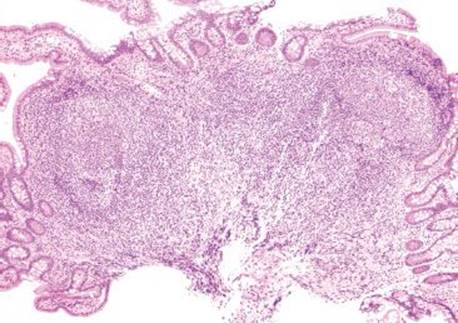

Answer: You are not alone! Prominent lymphoid aggregates can be especially alarming in the terminal ileum and, thus, are a common source of consultation. The small bowel serves as an essential component of the immune system through its perpetual surveillance of the passing luminal contents. Diligent immunosurveillance is facilitated through specialized epithelial cells (M-cells) that transport luminal antigens to the lymphoid aggregates (designated “Peyer patches” when seen in the terminal ileum). Hyperplastic lymphoid aggregates can be sufficiently large as to be visualized endoscopically and can also serve as intussusception lead points, especially in young children.5,6 The epicenter of lymphoid aggregates is in the mucosa but especially prominent cases can feature extension into the submucosa, raising concerns for a hematolymphoid malignancy. Histologic features reassuring for a benign, reactive process include the presence of germinal centers, tingible body macrophages, and a polymorphous constituent lymphoid population (i.e., a variety of cell sizes represented); however if the focus in question seems at all concerning, a quick immunohistochemical panel may be worthwhile (Figs. 3.19–3.37) (Table 3.1).

Figure 3.21 Normal terminal ileum. As this case illustrates, large lymphoid aggregates can occasionally extend below the muscularis mucosae (bracket) into the submucosa. Features in support of a benign process include variably sized lymphoid aggregates, germinal centers (arcs), tingible body macrophages (macrophages containing apoptotic debris in the cytoplasm, arrowheads), and a polymorphous lymphoid population (variably sized lymphocytes, best seen at high-power, Figures 3.29–3.30).